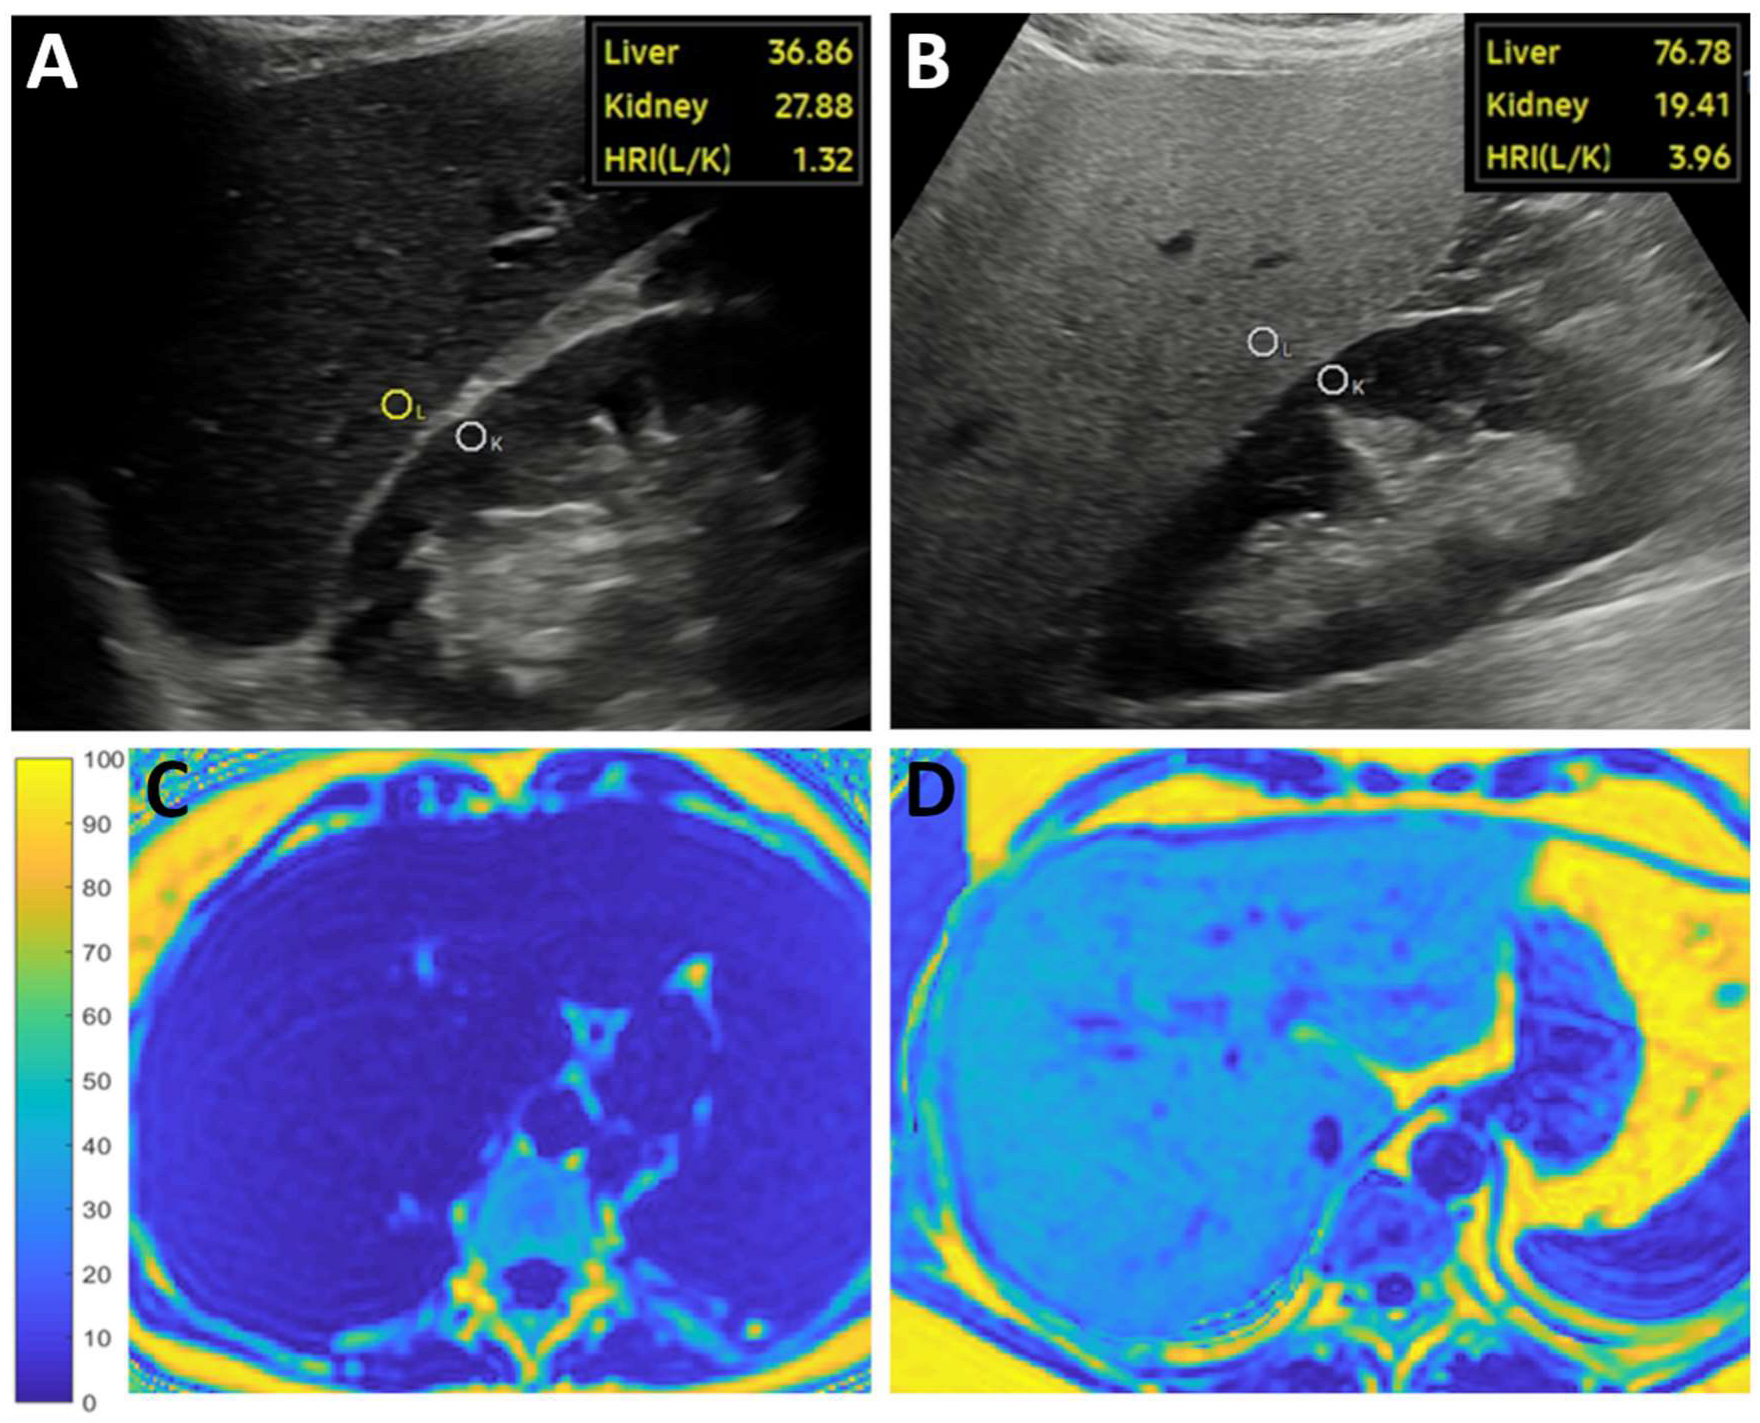

2.2. Ultrasound Scanning and AI-HRI Measurements